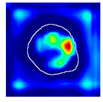

| True label: Crescentic |  |  |  |  |  |

| single-multiclass: Crescentic p = 0.999, IoU = 0.154 | |||||

| multiple-binary: Crescentic p = 1.000, IoU = 0.128 | |||||

| Spatially guided: Crescentic p = 0.979, IoU = 0.740 | |||||